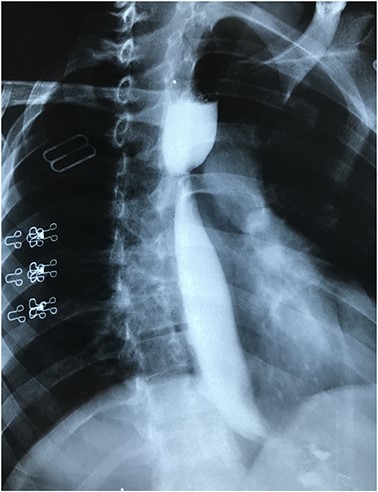

Barium study repeated after the endoscopic dilatation, which showed passage of the contrast agent to the stomach with no evidence of stricture (Fig. 3).

Barium study showing the passage of the contrast agent to the sleeved stomach with no evidence of stricture after successful endoscopic dilatation.